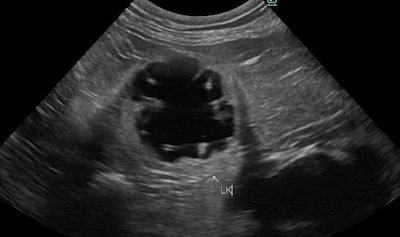

動物用CTを用いた検査が可能です。経験豊かな獣医師が患者様の状況に合わせて最善の検査・治療をご提案いたします。また、軟部組織外科など難度の高い手術症例にも対応しています。